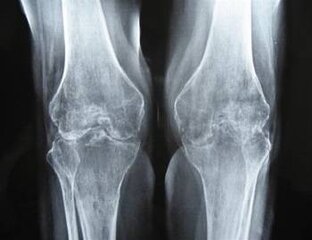

БОЛЬ В КОЛЕННОМ СУСТАВЕ. Остеоартрит.

Остеоартрит (остеоартроз).   Группа заболеваний, при которых поражаются все компоненты суставы (хрящ, кость, синовиальная оболочка, сухожилия, капсула, мышцы) - возникают микроповреждения, которые затем переходят в макроповреждения с локальным воспалением и прогрессирующей деструкцией. Это большая тема для обсуждения, про нее будет отдельный материал. Ускоряют развитие остеоартрита: травмы, избыточная физическая нагрузка, ожирение, дисплазия, метаболические заболевания, аутоиммунное поражение суставов...